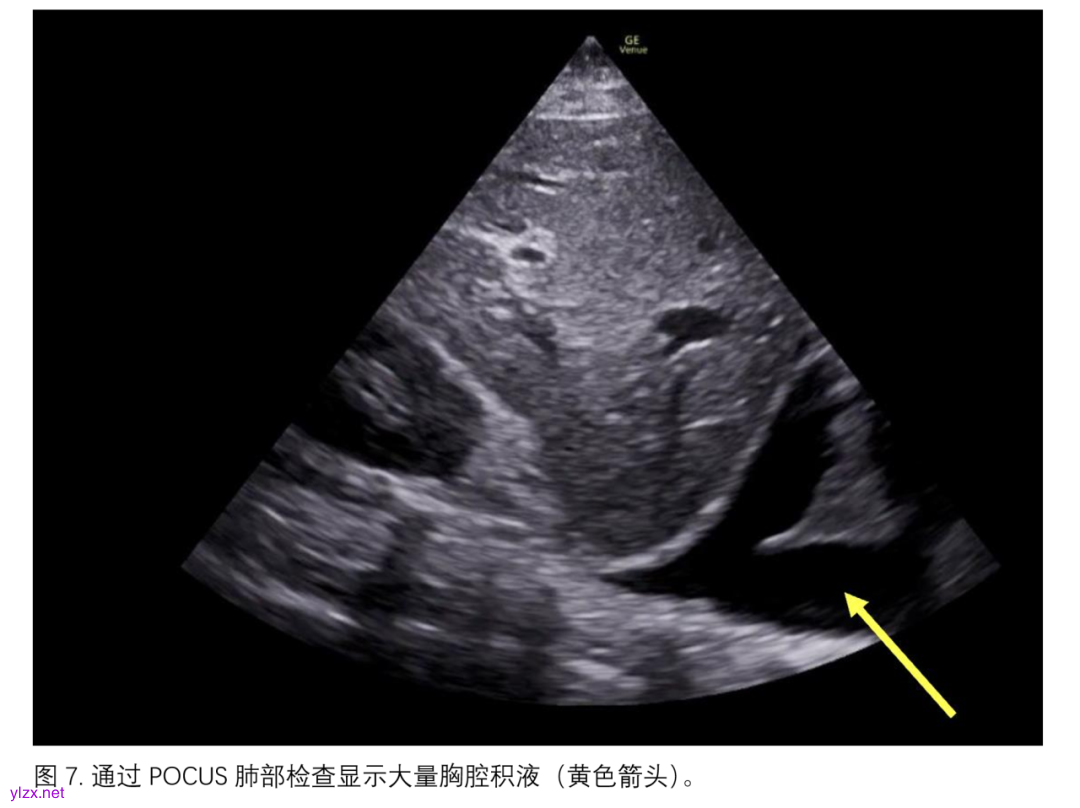

急性或慢性肺部疾病的加重也可能导致低氧血症恶化和/或急性右心室功能障碍,并随之引起肺血管的重塑。POCUS(超声心动图)已被广泛描述为一种敏感的检查方法,可用于检测新的气胸(通过“肺点”的可视化)、血胸或大量胸腔积液(图7),或肺部实变。此外,心脏POCUS和/或经食道超声心动图(TEE)已被用于ARDS患者中,以检测和评估新的急性右心室功能障碍的严重程度,表现为右心室扩张、估算的肺动脉压力、室间隔运动异常和右心室肥厚,这些指标可能对药物治疗和/或通气策略的选择以及预后具有重要意义。